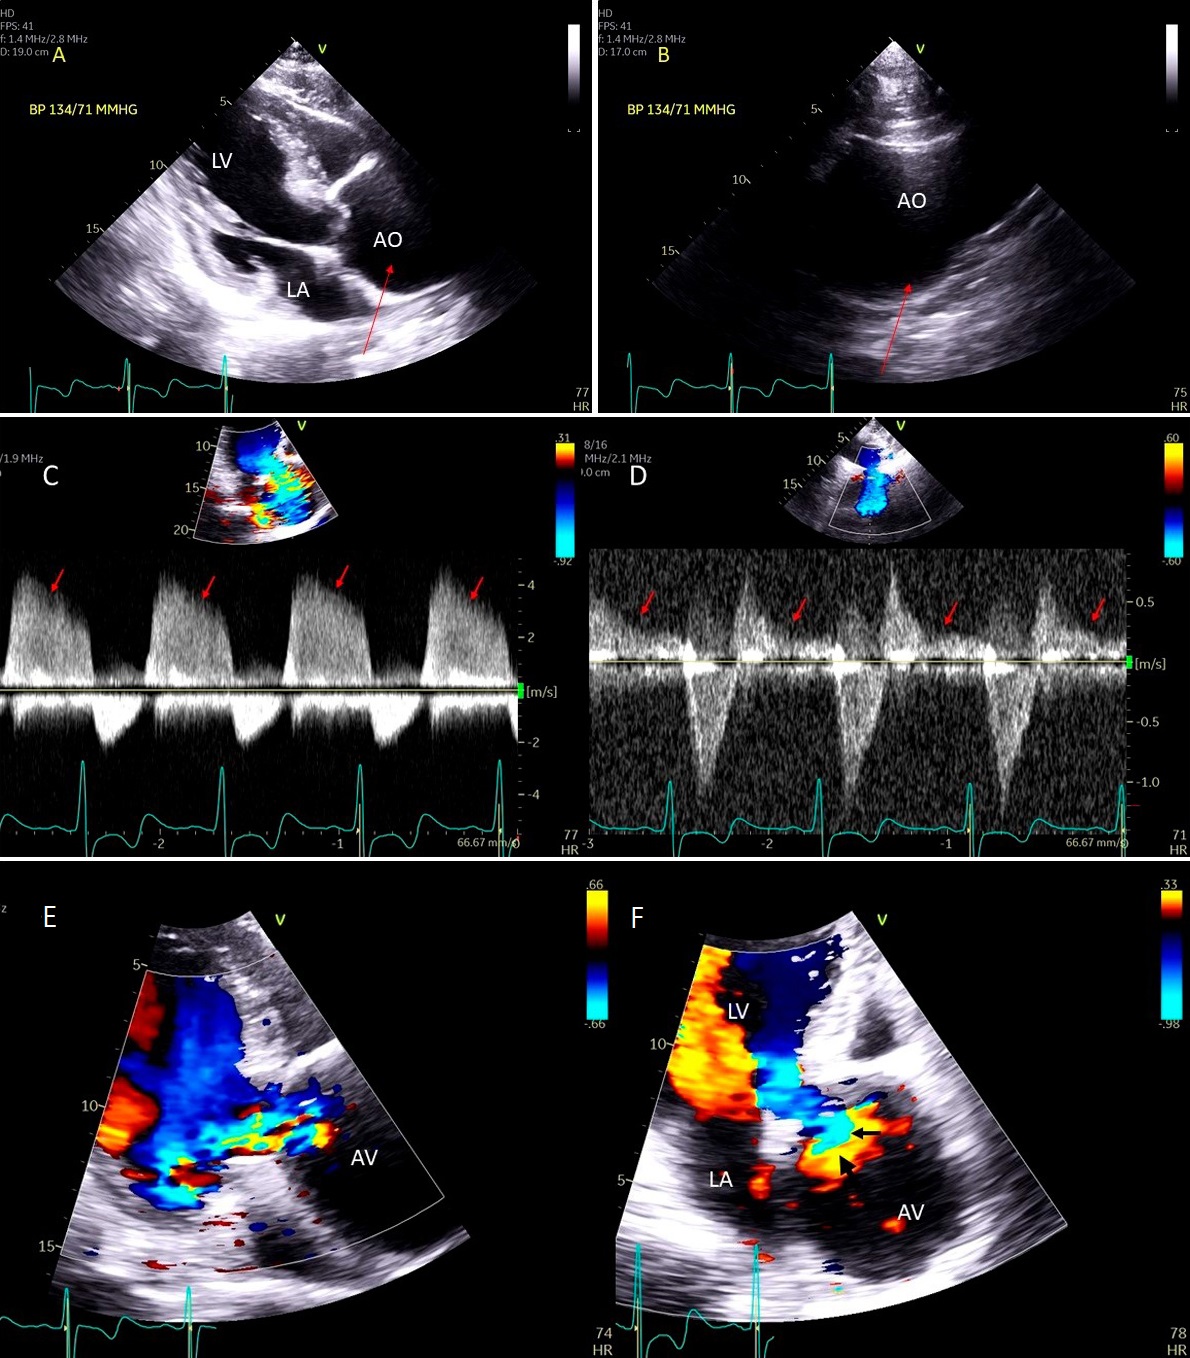

Fig. 4.Functional Tricuspid regurgitation. (A) TEE mid esophageal inflow-outflow view shows a dilated RV and tricuspid annulus (white arrows). (B) TEE 4 chamber view color Doppler showing centrally directed severe tricuspid regurgitation with PISA (white arrows). (C) PW Doppler showing systolic hepatic flow reversal, which suggests severe TR (red arrows). RA; right atrium; RV, right ventricle; AO, aorta.